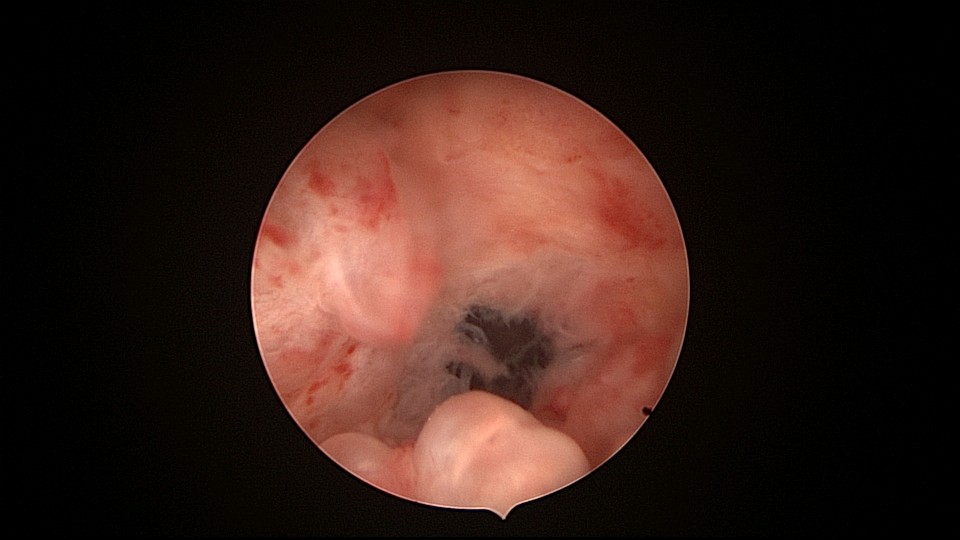

患者81岁,G5P5,顺产5次,安环50年,绝经23年,高血压病史多年,10年前因颅内肿瘤行开颅手术,4年前行腹腔镜胆囊切除术,外院介绍到我院宫腔镜取环。子宫前位,宫颈萎缩,穹隆展平,宫颈外口位于穹隆偏左侧,平滑狭小,夹持宫颈很困难,阴道内镜方式进入宫腔,见宫腔下部O型环圈内前后壁粘连,顿性分离粘连,宫腔中上部O型环与两侧宫壁嵌顿,异物钳松动节育环,但难以取出,取环钩沿镜鞘外侧进入宫腔,配合中弯钳牵拉出节育环,环变形,检查环完整,宫腔无其他异常。